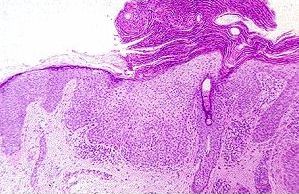

Histologically, the following features are noted (note: the main feature of actinic keratosis is dysplasia without invasion):

• hyperkeratosis (increased amount of keratin)

• parakeratosis (presence of cell nuclei in the keratin layer, this is a sign of decreased turnover time of the epidermis)

• dysplasia (abnormal maturation of the epidermis; the cells have atypical morphology cytologically)

• solar elastosis (in which the dermis is stained blue rather than pink resembling the elastic tissue; this is a sign of sun damage)

Actinic keratosis with all the typical features:

hyperkeratosis, parakeratosis, dysplasia and solar keratosis.

Higher magnification showing dysplasia in actinic keratosis.